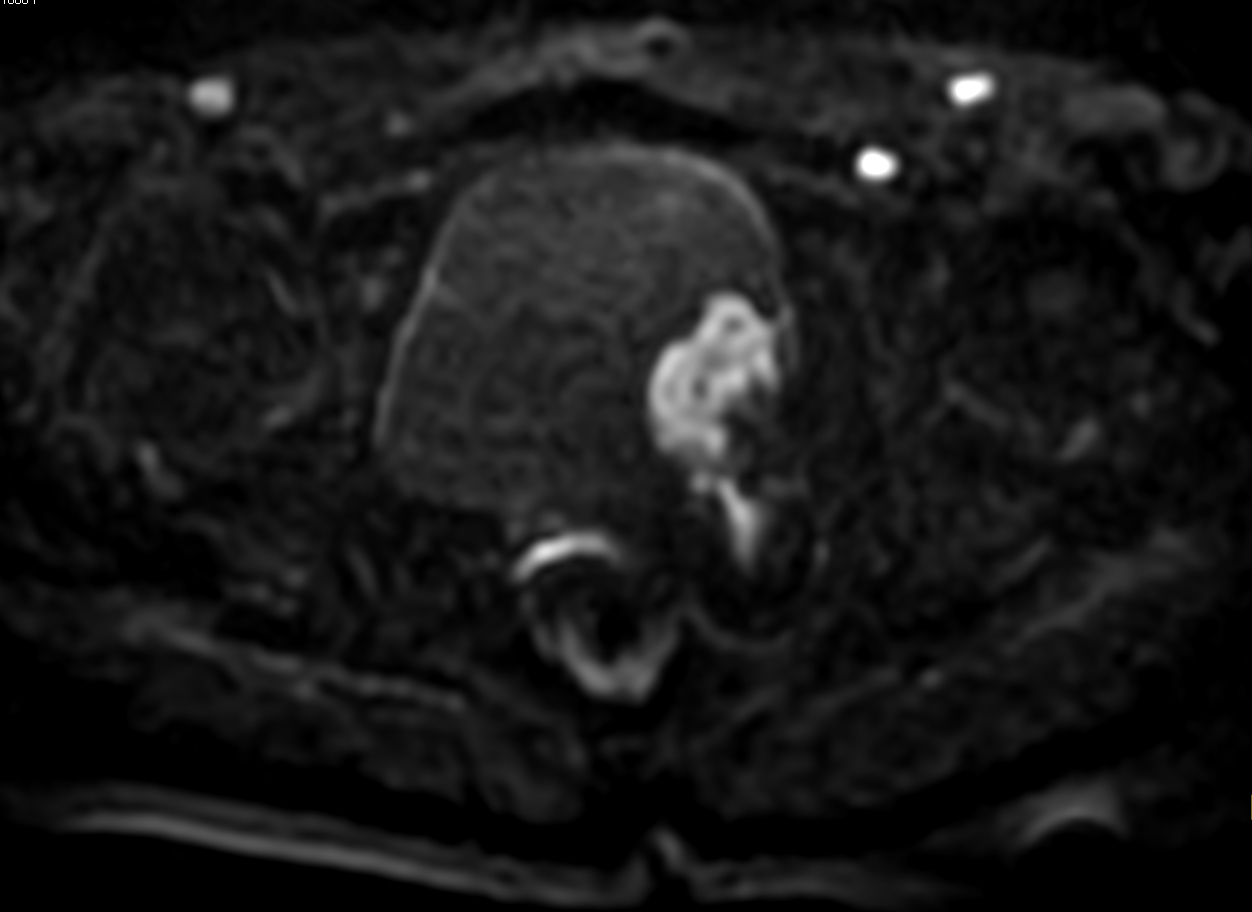

DWI b1000

DWI b1200